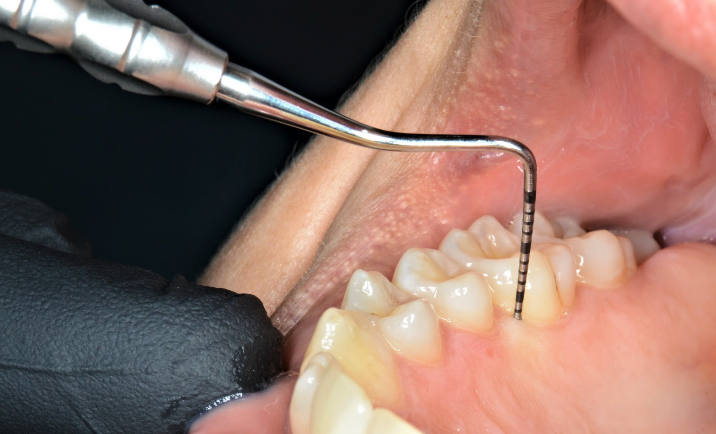

Dacă aveți vreo suspiciune că aveți o suferință de natură parodontală, sau dacă medicul dumneavoastră stomatolog observă o asemenea afecțiune, primul pas este o vizită la medicul parodontolog. Acesta vă va efectua un consult complet, însoțit de realizarea unei fișe parodontale, ce va urmări măsurarea gingiei din jurul fiecărui dinte cu ajutorul unui instrument cu gradații (Fig. 5.3.1). În funcție de aceasta se va pune un diagnostic și se va recomanda un plan de tratament aferent.